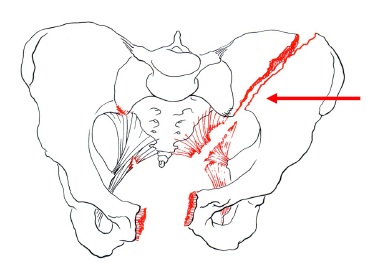

Wie klassifiziert man Beckenfrakturen? Typ A Nenne drei Beispiele: Nach der ABC Klassifikation nach AO & Tile. Typ A: Stabile Beckenringsfraktur. Im hinteren Beckenring Stabilität intakt Vertikaler Kraftfluss auf das Femur stabil. Z. B. Fraktur des Beckenrandes, des vorderen Beckenringes, von Os sacrum/Os coccygeum

Typ B Beckenringverletzung mit rotatorischem Stabilitätsverlust mit inkompletter Durchtrennung des hinteren Beckenrings und erhaltener vertikaler Stabilität -> Partiell instabil. Beeinträchtigte Stabilität im hinteren Beckenring, Rotationsstabilität einer Beckenseite.

Was sind Beispiele für Typ B? Nenne drei: Typ B1: Symphysensprengung ("open-book") Typ B2: Laterale Kompressionsverletzung Typ B3: Beidseitige B-Verletzung

Typ C Instabile Beckenringsfraktur mit Rotations- & Translationsinstabilität. Komplette Instabilität des hinteren Beckenrings, Rotationsinstabilität einer Beckenseite.

Was sind Beispiele für Typ C? Nenne drei: a) Schädigung von Os sacrum, -ilium oder Iliosakralgelenk sowie Symphysensprengung/vordere Beckenringfraktur b) C-Fraktur + B-Fraktur auf der Gegenseite c) Beidseitige C-Fraktur

Wie sehen Frakturen Typ A - C aus?